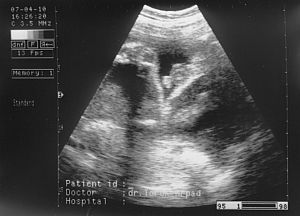

Ez a kis arca, szembööl. Kép

Ez az elsöö kukis képe 27. hetesen :-)

Kép

Második kukis kép 29 hetesen :-) Kép

ès itt van öö, profilbol. Kép

Nagyon utálta az uh-t, a kis keze ott van az arcocskája elöött. Remélem, hogy minden kivehetöö.

Kata: Nagyon édi!! A 29 hetest nem tom kivenni :oops:

Ott rajta van az egész lábacskája, ahogy kicsit összehúzza és jobb oldalt, a combjánál látszanak a kis heréi. :D